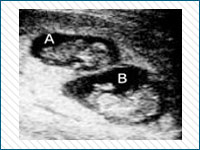

Pregnant?